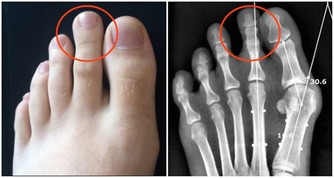

4.不凍腳

俗話說:養樹需護根,養人需護腳。腳作為人體的“第二心臟”,一旦受寒,容易引起腰腿疼痛、骨刺等問題,還會增加心血管疾病的患病概率。

建議:把涼鞋收一收,換上棉襪布鞋。家里地板是瓷磚的朋友,也別光著腳走,把鞋子穿上。